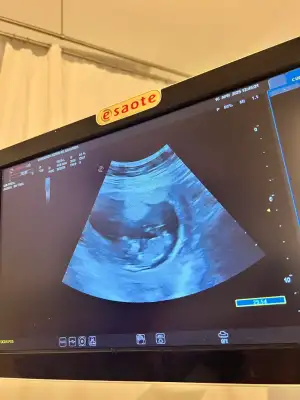

İpucu verir misiniz

Sanki bir çıkıntı var gibi ama kordon da olabilirİpucu verir misiniz

Hayır bir şey söylemedi ama çok hareketliydiSanki bir çıkıntı var gibi ama kordon da olabilirdoltorunuz bir tahminde bulunmadı mı

Allah allah ultrosonda baya netmiş gözükürdü aslındaHayır bir şey söylemedi ama çok hareketliydi

Bilemedim kiAllah allah ultrosonda baya netmiş gözükürdü aslında

Plesenta konumuna göre tahmin edilebiliyormuş sanırım. Kendi görüntümüzde fark edemediğim için bir tahminde bulunamadım ve çok merak ediyorum. Siz de kontrol edebilirsiniz.12 haftaligiz cinsiyet hakkında tahmini olan var mı

Ben fotoğraftan erkek hissettim ya. Siz ne hissediyorsunuz?Bacak arası bariz açıktı baktık çıkıntı görünüyor sonra doktor bu haftalarda kız bebeklerde de şişlik olabilyor dedi o yüzden 16. Haftayı bekleyeceğiz mecburen meraktan çatlarım o zamana kadar

Bu da benim bebişBacak arası bariz açıktı baktık çıkıntı görünüyor sonra doktor bu haftalarda kız bebeklerde de şişlik olabilyor dedi o yüzden 16. Haftayı bekleyeceğiz mecburen meraktan çatlarım o zamana kadar